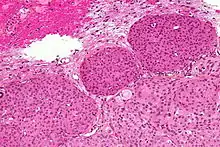

Histologically, meningioma cells are relatively uniform, with a tendency to encircle one another, forming whorls and psammoma bodies (laminated calcific concretions).[16] As such, they also have a tendency to calcify and are highly vascularized.